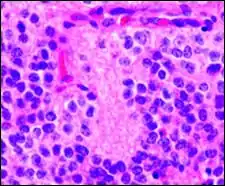

Pineocytomatous/neurocytic pseudorosettes

Histologic features of these two tumors are virtually identical, including their tendency to form neuropilrich rosettes, referred to as pineocytomatous/neurocytic rosettes in central neurocytoma. Both are quite similar to the Homer Wright rosette, but they are generally larger and more irregular in contour. The cells of the pineocytomatous/neurocytic rosettes are also considered to be much more differentiated than the cells forming Homer Wright rosettes in that the nuclei are slightly larger, more rounded, much less mitotically active, and paler or less hyperchromatic. In rare cases, these rosettes may aggregate in a sheet of back-to-back clusters resembling field stone pavement.[2]

Micrograph of pineocytomatous/neurocytic pseudorosettes